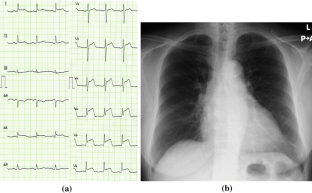

A 78-year-old woman was referred to our hospital because of general fatigue. The electrocardiogram showed ST elevation in the I, II, aVL, and V2–V6 leads. Echocardiography showed left ventricular apical akinesis. On emergent cardiac catheterization, left ventricular basal hyperkinesis and apical akinesis without coronary artery stenosis were found. The patient was diagnosed with Takotsubo cardiomyopathy. Two-dimensional myocardial speckle tracking echocardiography was performed on admission, the 8th hospital day, and the 15th hospital day. Gradual improvement in wall motion abnormality and longitudinal peak systolic strain, peak systolic strain rate, and early diastolic strain rate from the basal to apical region of the left ventricle were observed objectively, and she achieved remission. We herein report a case of Takotsubo cardiomyopathy in which objective improvement in left ventricular contraction and relaxation was observed by 2D speckle tracking imaging and bull’s eye mapping.

Fig. 1